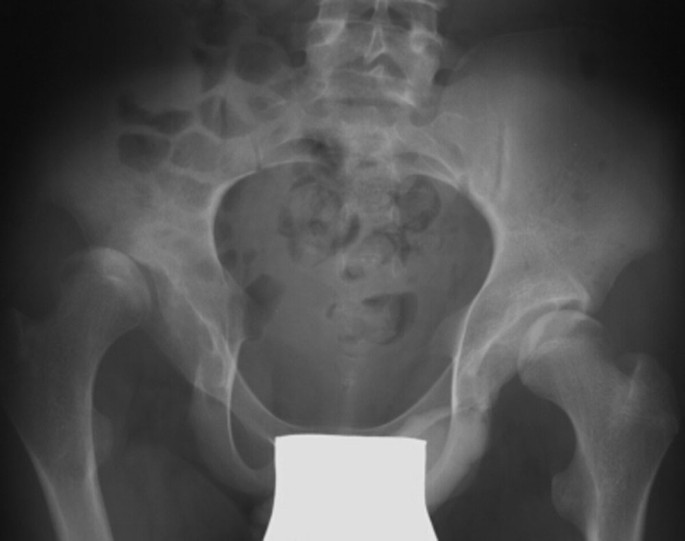

De meest voorkomende complicaties zijn een vernauwing stenose van de cervicale opening en een uitgestelde menstruatie.